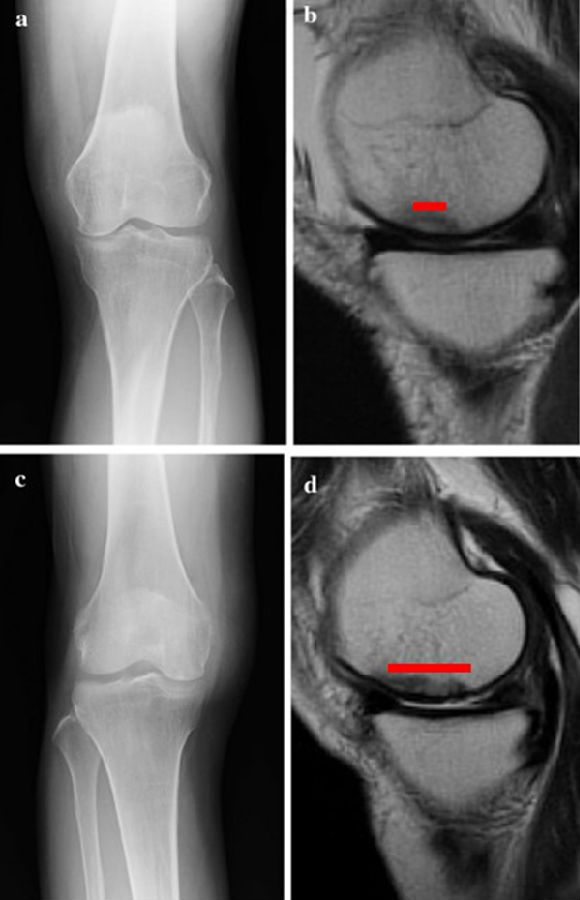

a.患者,59岁女性,AP侧位片显示SONKⅠ期,FTA<180°;b.MRI T2显示病变深度<20mm,患者出现症状1年后保守治疗;c.75岁女性,X线显示SONKⅠ期,FTA>180°;d. MRI T2显示病变深度>20mm,患者于症状出现后11周行手术治疗